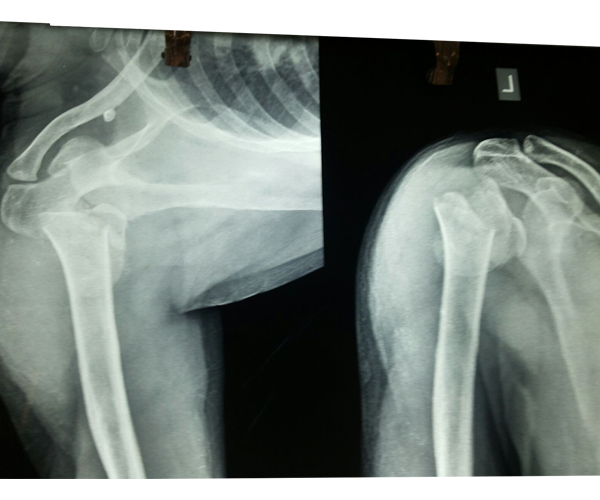

Case:17 Bilateral Fracture Dislocation

Known case of Epilepsy in 45-year-old Mason treated with open reduction & internal fixation with philos plate & locking screws bilaterally.

Right side Pre-Op

Right side Post-Op

Left Side Pre-Op

Left Side Post-Op